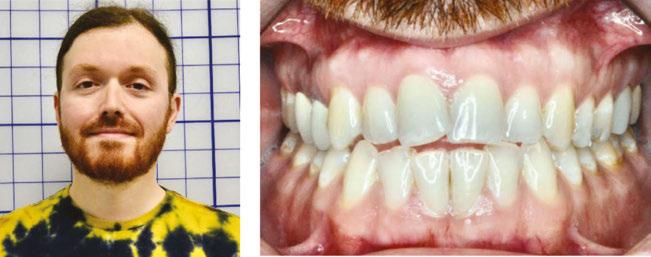

tan was referred to my office by a TMD specialist. His chief complaints were he could not chew or open his mouth without pain. It seemed the less he chewed, the more pain he experienced. As a result, an Orofacial Myofunctional Therapy (OMT) program was created to help support his muscles of the TMJ and craniofacial respiratory complex. He used his splint as instructed by his specialist. However, his anterior open bite widened, and his teeth became more misaligned over time.

Stan was a 28-year-old male in a lot of pain. He had just come from his TMJ specialist where he received an oral orthotic splint to relieve his discomfort. He told me it all started after a long dental appointment where he received a root canal and a new crown on the upper right. After this procedure, his jaws felt tight so he gave it a good stretch by opening very wide. He heard a rip and a crunch. Opening his mouth was never the same after that. He presented with a set of symptoms: TMD muscle pain, he could no longer chew his food without pain (food had to be the soft consistency of tofu), daytime clenching and night time grinding of his teeth. In addition, he had daily headaches and ear ringing. He could not open his mouth very wide without experiencing sharp pain. He took acetaminophen for his discomfort and zolpidem nightly to help him fall asleep easier.

An orofacial therapy program was created to allow his tongue to give better support and function to his oral structures, especially the TMJ joint. When the tongue naturally rests in the palate, it removes the unwanted pressure off of the TMJ. As part of the course of his therapy, focus was made to reeducate his breathing to make his nose the primary way he breathes. Optimal breathing rate for an adult is slower than for a child. Good nasal breathing during the day supports good nasal breathing during the night for optimal sleep. When the tongue rests in the palate, it impacts facial development especially for children who are still growing. An adult, for example, like our friend Stan, the progress made is gradual but more likely to last a lifetime. Generally, therapy starts out once a week for about 2-3 months. Then therapy progresses to every other week for 2-3 months, and then changes to once a month for about 5 months for the rest of the year. The exercises are done a minimum of 2 times everyday. These exercises are designed to strengthen and tone the orofacial muscles, building brand new neuromuscular function. When the muscles of the face are well developed, it may favorably impact appearance and the overall integrity of the facial structures. The muscles of the face also include the tongue, lips, cheeks and neck. Although the therapy program is typically only a year, Stan really liked how good he felt and decided to continue with some of the exercises to this day. From the photos you can see how much the program has impacted his health and well-being.

After completing his course of myofunctional therapy, he was able to open his jaws with full range of motion and achieve his goal of being able to enjoy some of his favorite foods again. He was most excited about being able to bite into a juicy cheeseburger.

To document any initial assessment, the midpoint of therapy, and when therapy has ended, it is important to take detailed photos, videos, plus full measurements of the face and teeth. This makes it possible to compare results while showing that your therapy works based on the evidence you gathered before, during, and after treatment.